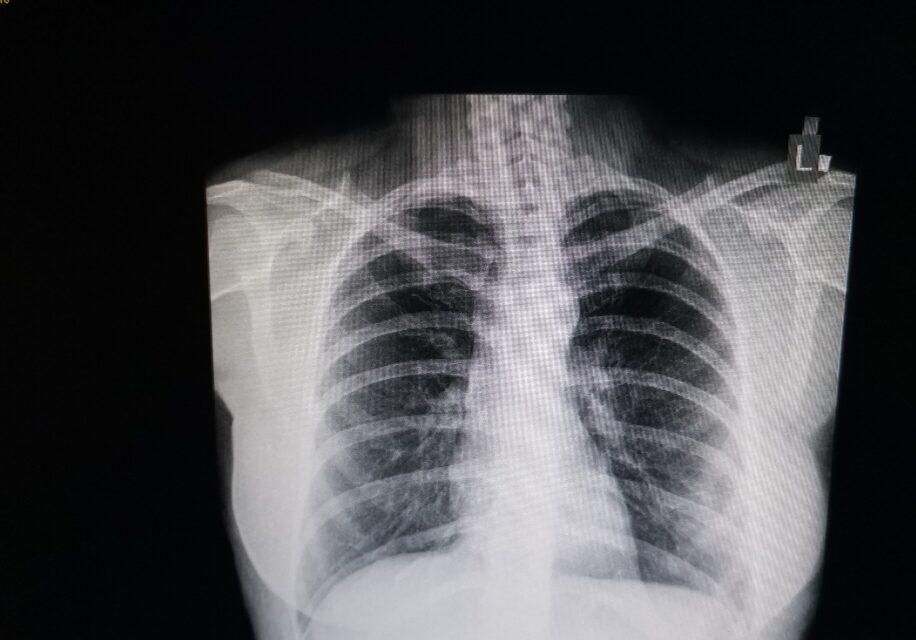

Pregled je besplatan, a obavlja se metodom niskodozne kompjuterizovane tomografije (CT). Za zakazivanje pregleda potrebni su lični podaci (ime, prezime), datum rođenja ili jmbg i kontakt telefon.